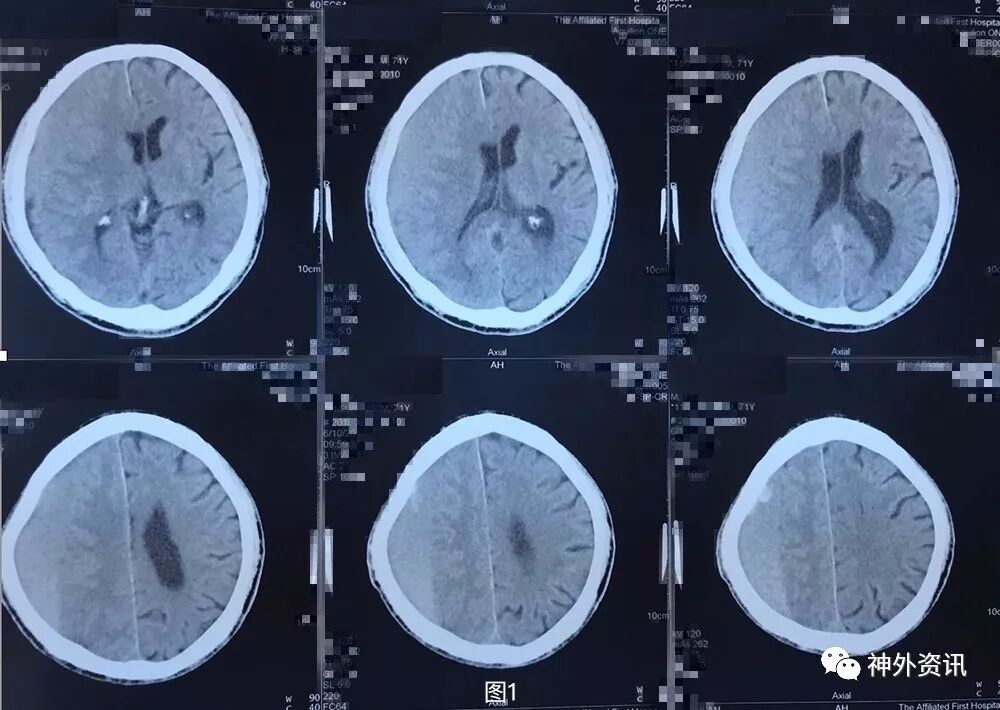

患者5月前不慎头部外伤,当时无黑懵晕厥,无头痛头晕,未重视治疗,3月余前无明显诱因下出现头痛,伴头晕,伴行走不稳,前往外院就诊,查头颅CT示:右侧额颞顶枕部慢性硬膜下血肿考虑(图1),行钻孔引流术。术后复查头颅CT提示右侧额颞顶枕慢性硬膜下血肿钻孔引流术后改变(图2),术后症状好转出院。2月前(术后1月)患者再次出现头痛晕头晕等症状,复查头颅CT:右侧额颞顶枕硬膜下血肿,脑实质受压,中线轻度左偏(图3)。遂再次行右额颞顶枕部硬膜下血肿钻孔引流术,术后患者头痛无明显好转,伴左侧肢体乏力,复查头颅CT见术后局部血肿形成(图4)并进行性增大(图5)。

图1. 外院第1次术前头颅CT提示:右侧额颞顶枕慢性硬膜下血肿考虑。血肿为稍高密度,伴局部高密度。